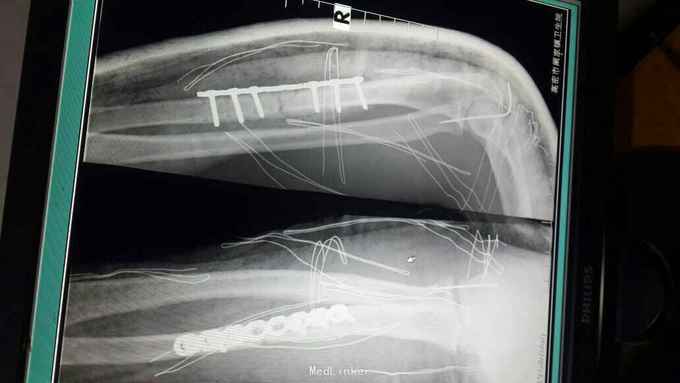

右孟氏骨折

骨折 孟氏骨折

患者,男,21岁。摔伤右前臂肿痛畸形1小时。患者1小时前骑摩托车时不慎摔倒,伤及右前臂,当时即感肿痛畸形不敢活动,院外未治疗来诊。

右前臂肿胀明显,可触及骨擦感及异常活动,肘关节屈伸疼痛,不敢旋转。末梢血供感觉正常。

右孟氏骨折的上尺桡关节脱位如何处理比较好